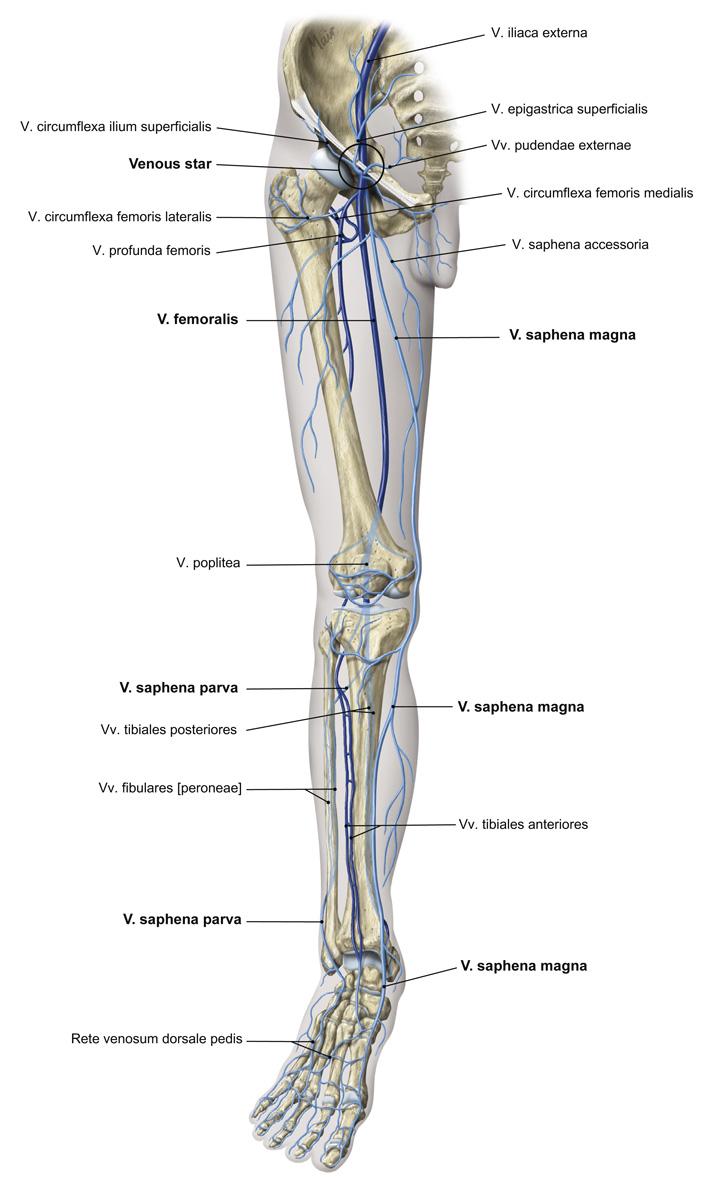

Fig 3.37: Oppervlakkige aders van het been

-

diepe bloedvaten

malleolus lateralis malleolus medialis rete venosum dorsale pedis -

v saphena magna (voor malleolus medialis, via hiatus saphenus naar v. femoralis)

v saphena parva (achter malleolus lateralis, tussen koppen m. gastrocnemius, naar v. poplitea in fossa poplitea) v saphena accessoria (via hiatus saphenus naar v saphena magna)